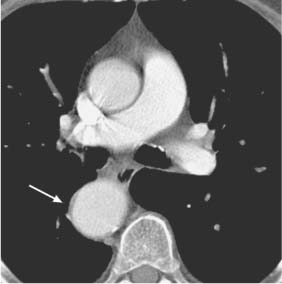

Computed Tomography Radiology Key Computed tomography modern radiology is a free educational resource for radiology published online by the european society. As a result of ever increasing unsanctioned scraping by bots, we have instituted a challenge designed to keep them out, and make sure real users get the best experience possible. if you're not a bot, you shouldn't see this error. if it persists, please contact [email protected] and we'll help to unblock you. Computed tomography (ct) is defined as a medical imaging technique that measures the intensity attenuation of x ray beams from multiple orientations to create cross sectional images, utilizing a scanner comprised of an x ray source and a series of detectors. The evolution of x ray computed tomography (ct) has been based on the discovery of x rays, the inception of the radon transform, and the development of x ray digital data acquisition systems.

Computed Tomography Radiology Key Computed tomography (ct) is defined as a medical imaging technique that measures the intensity attenuation of x ray beams from multiple orientations to create cross sectional images, utilizing a scanner comprised of an x ray source and a series of detectors. The evolution of x ray computed tomography (ct) has been based on the discovery of x rays, the inception of the radon transform, and the development of x ray digital data acquisition systems. It begins by introducing ct and comparing it to conventional radiography. ct provides more accurate diagnostic information by reconstructing 3d structures from multiple 2d projections, unlike conventional radiography which produces 2d shadow images. The main advantages of ct over conventional radiography are with ct, the superimposition of structures is minimized with ct, the ability to differentiate small differences in density according to their individual shades of gray is maximized. Purpose: we provide a review of the key computed tomography (ct) technologies developed since the late 1980s and offer an overview of one of the future technologies under development. the focus of this review is mainly on the hardware and system development. This article examines the key physical principles and technical features of the ct scanner, highlighting significant developments in ct technology that have led to the creation of helical, multidetector, cone beam, portable, dual energy, and phase contrast ct.